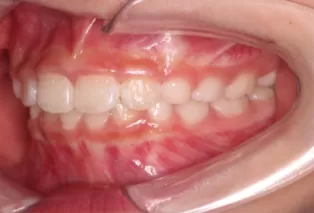

Intraoral photos